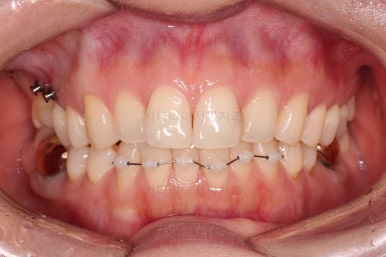

마찬가지로 부산치아교정비용 초진 시 입안의 모습입니다.

아랫니가 많이 보이지 않는 타입이라서 잘 몰랐는데 입안을 관찰해 보니 아래 앞니가 삐뚤어 있네요.

이 부분도 꼭 교정해야 될 정도는 아니여서 선택의 문제라고 할 수 있는데요.

이번 환자분이 선택한 앞니 부분교정 장치는 MTA라는 장치인데요.

부분교정에 좀 더 특화된 부피가 작고 심미적인 장치입니다.

물론 철사는 들어가고요.

치료 종료시의 모습인데요.

임플란트가 잘 들어갔고 아래 앞니도 원하는 모습으로 잘 배열이 되었습니다.